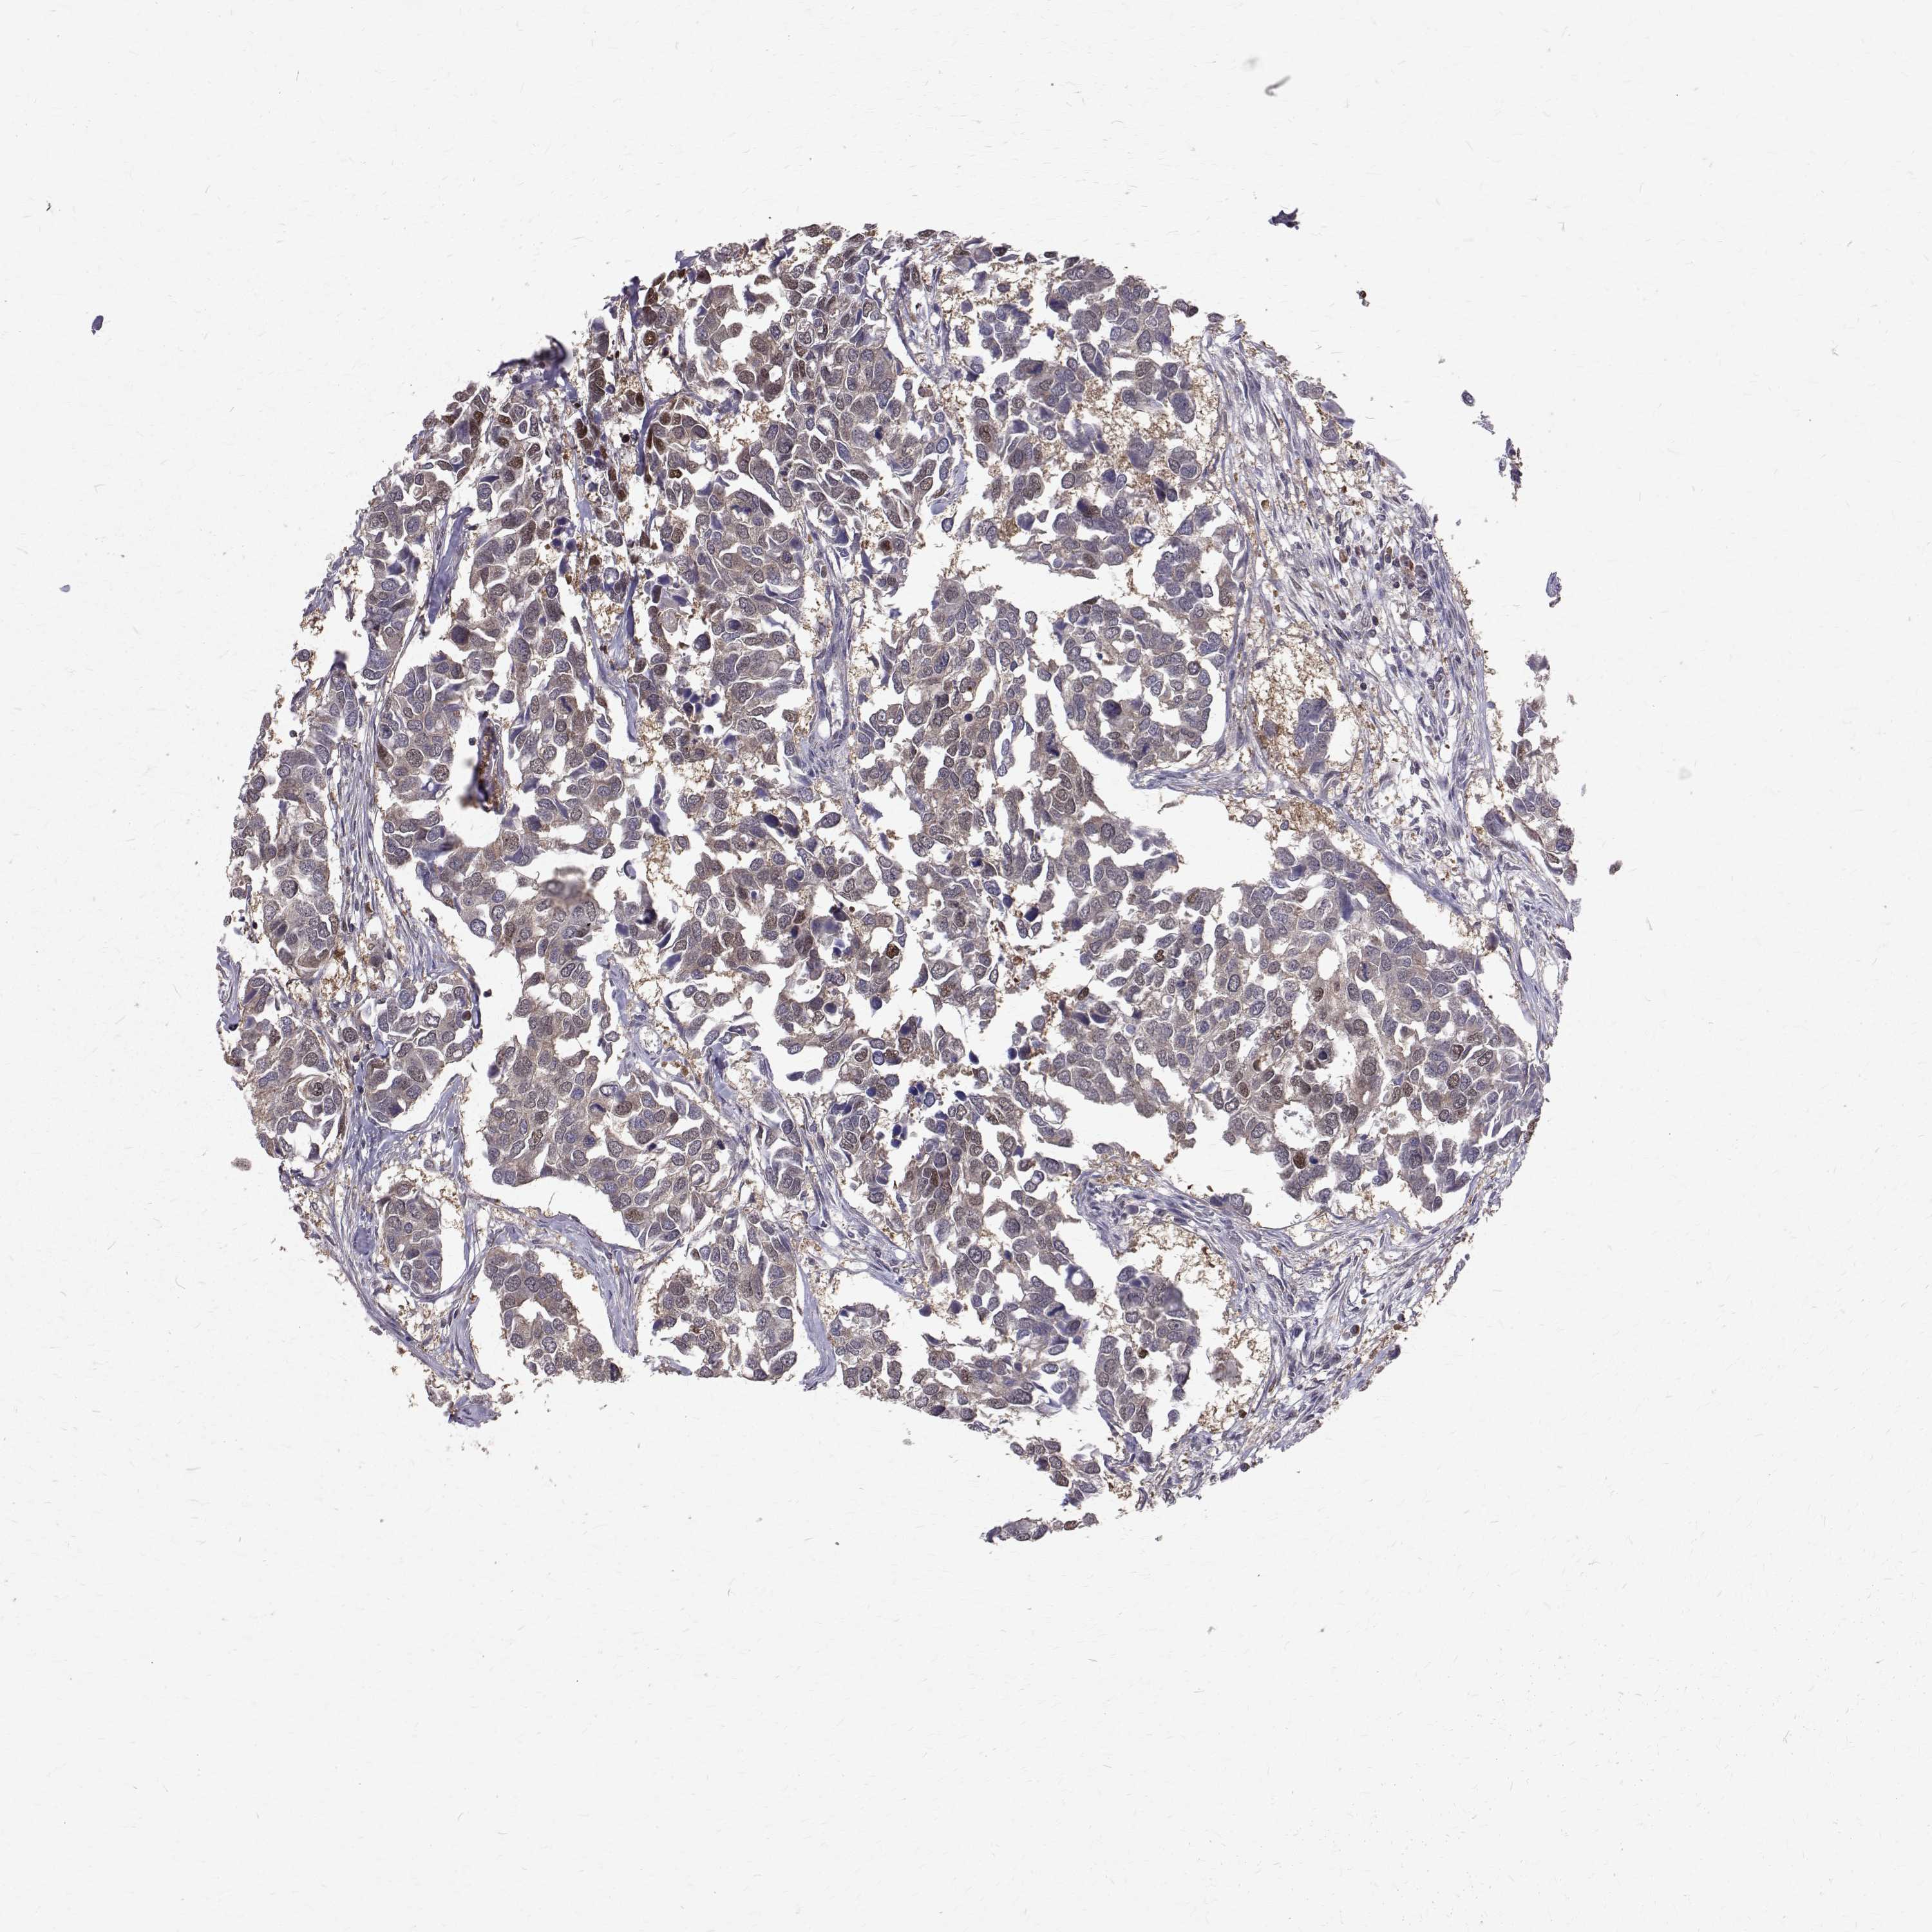

CANCER BREAST CANCER Show tissue menu

BRCA TCGA BRCA VALIDATION PROTEIN EXPRESSION

Breast cancer

Human cancer